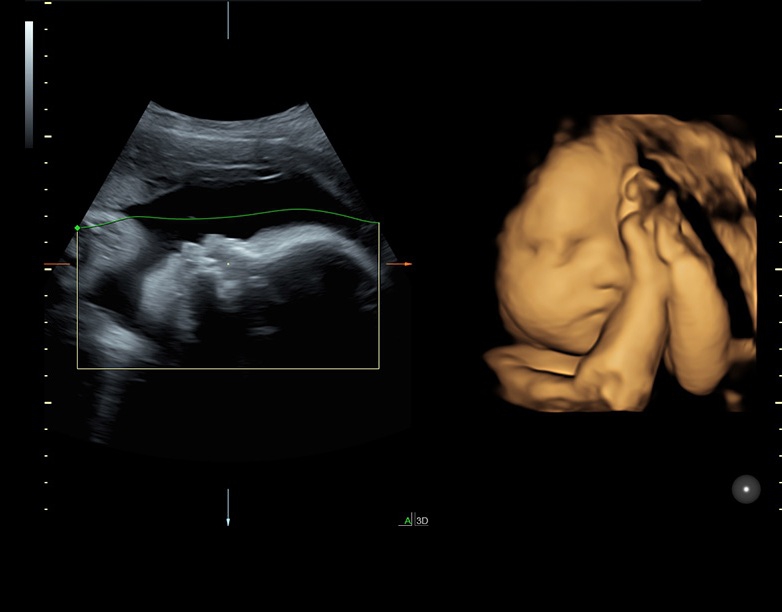

• Технология SonoRenderlive: Эта технология облегчает получение 3D/4D изображений путем автоматического изменения положения плоскости визуализации в зависимости от движений плода. Она позволяет получить реалистичные и объемные изображения, что полезно для демонстрации плода будущим родителям и для дополнительного анализа.